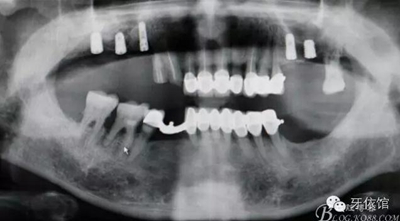

植入植體同時GBR

縫合

術(shù)后X光片